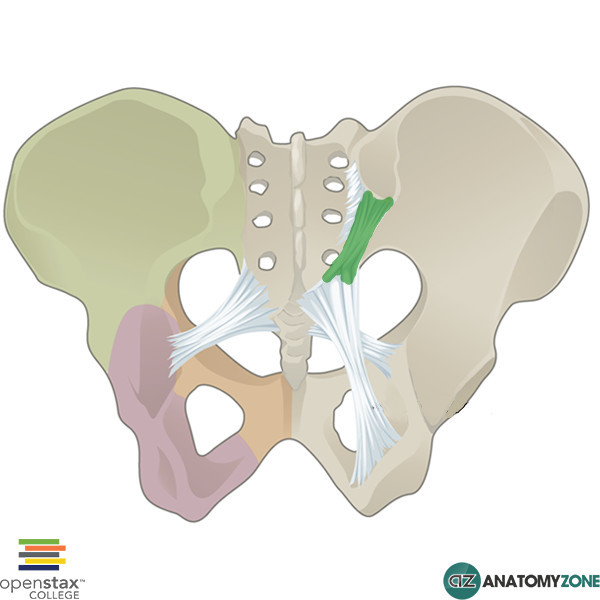

What is this structure?

Sacrospinous ligament